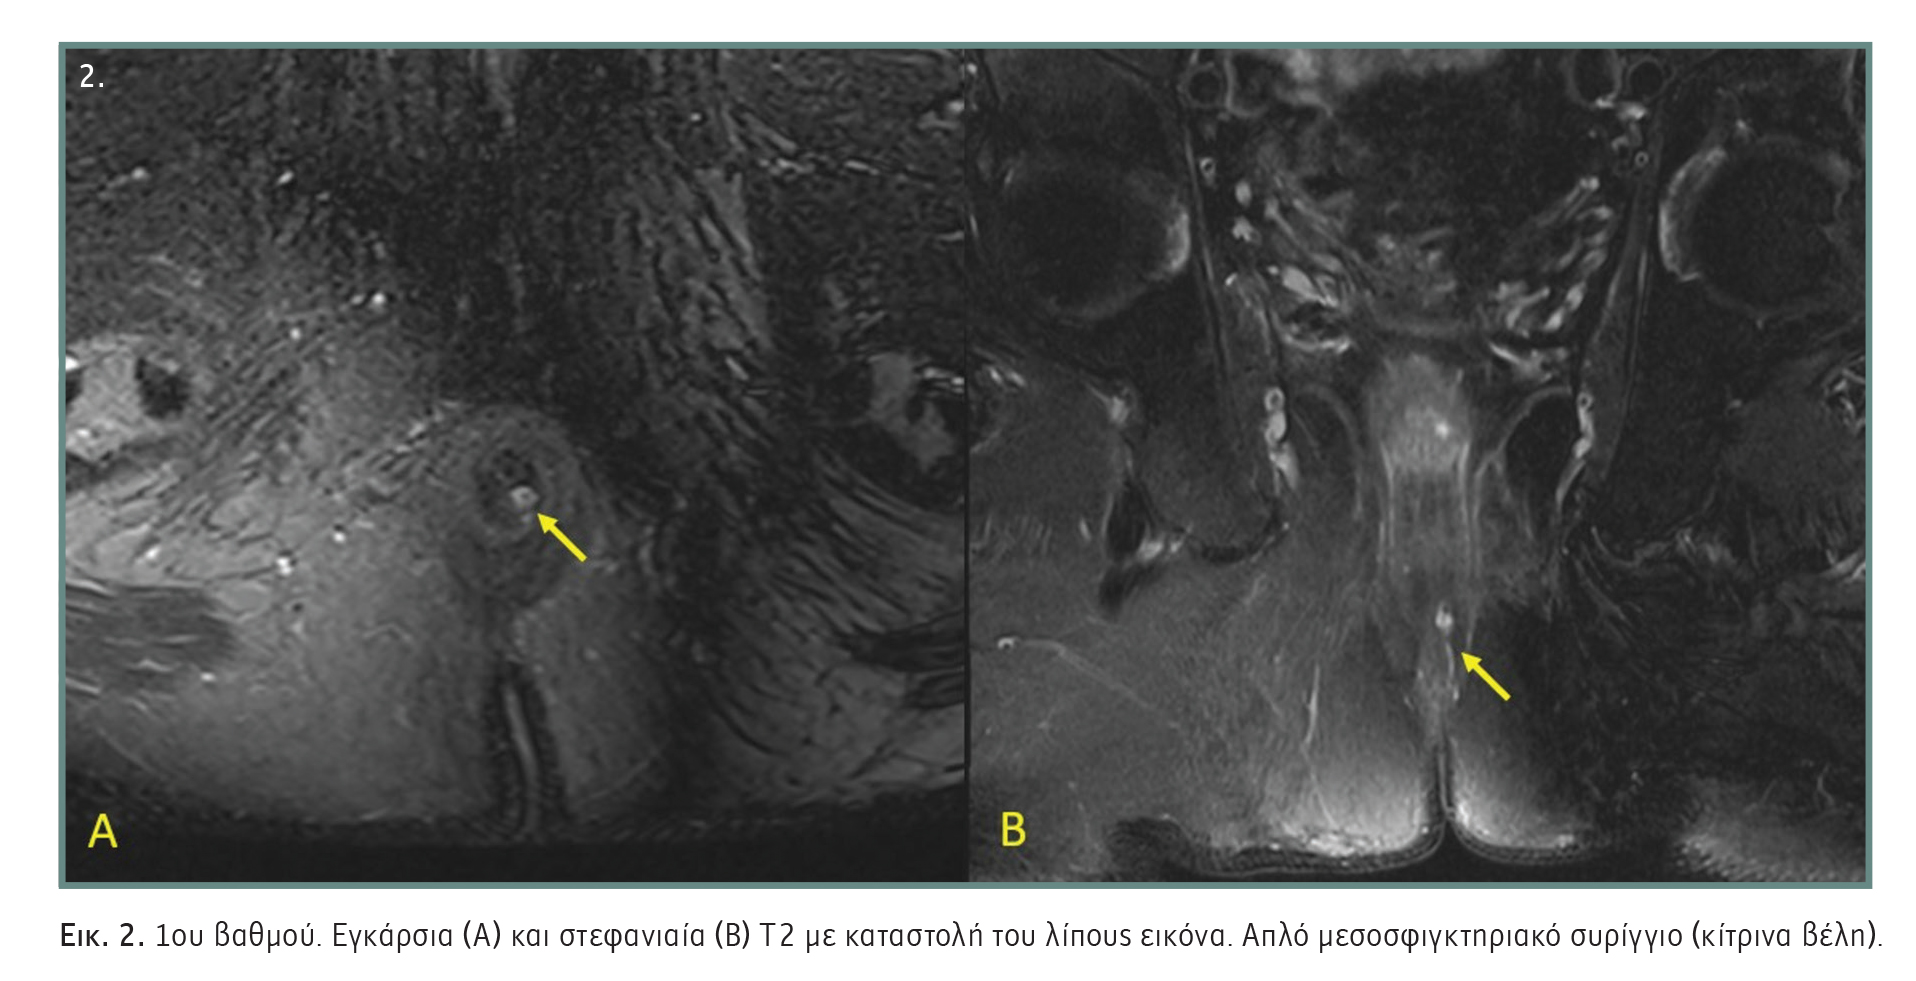

- 1ου βαθμού: Απλό γραμμικό μεσοσφιγκτηριακό συρίγγιο, το οποίο εκτείνεται από τον πρωκτικό σωλήνα μέσω του μεσοσφιγκτηριακού χώρου έως το δέρμα του περινέου. Δεν υπάρχει διακλάδωση του πόρου εντός του σφιγκτηριακού συμπλέγματος. Ο συριγγώδης πόρος περιορίζεται πάντοτε στον μεσοσφιγκτηριακό χώρο (Εικόνα 2).